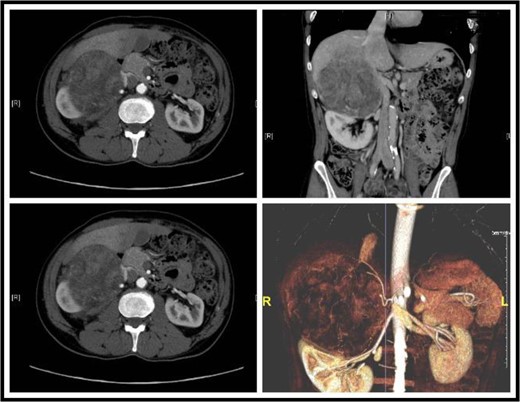

Sections of the CT showing a large retroperitoneal mass, focal absence of fat gland and an invasion into the liver.

Adrenohepatic fusion is a relatively common observation during autopsies [1]; however, neoplasms arising from the union are very poorly reported. In our case, an adrenohepatic fusion was detected using a CT scan of the abdomen that showed focal areas of loss of fat gland between the retroperitoneal mass and the liver. Dolan defined adrenohepatic union as the adhesion of the liver and the right adrenal cortex with the partial or complete absence of a fibrous capsule dividing the two organs [2]. Adrenocortical adenoma arising from an adrenohepatic union was reported in several cases [3]; however, we could not find a report that describes an adrenocortical carcinoma combined with a HCC from an adrenohepatic union in the literature as the case we present here. A differential diagnosis of HCC must be considered in such a case as the histopathology of the resected lesion shows mixed malignancies of adrenocortical carcinoma in the adrenal part of the lesion and a HCC in the hepatic part and several cases were reported in the literature of a primary HCC extending into the right adrenal directly [4], or to both adrenals as the first presentation of HCC metastasis [5], other reports mentioned cases where an HCC has developed in an ectopic liver tissue [6]. On the other hand, an adrenocortical tumor that developed from an adrenal rest inside the liver with radiological findings of HCC was also reported [7]. Okuda introduced a few cases of HCC presenting as pedunculated masses outside the liver most of which had dual blood supply of a hepatic and a suprarenal artery that might support the fusion phenomenon, furthermore, none of the masses were discovered in the left adrenal, which, again, supports fusion and invasion rather than hematogenous spread [8]. Core biopsy was reported in different similar cases to be of diagnostic value that changed the presumed diagnosis based solely on imaging modalities [5]. In our case, after using a CT scan to diagnose the patient, a trucut biopsy was done to confirm the diagnosis of an adrenocortical carcinoma invading the liver; however, an incidental histopathologic finding of co-occurrence of a HCC in the same lesion raised our suspicions, so we went to do a positron emission tomography scan CAP to look for any focus of metastasis, which revealed negative results. Surgical resection is the gold standard option to manage both HCC and adrenocortical carcinoma [5]. The patient was followed up for 2 years after the operation without evidence of metastasis or recurrence.